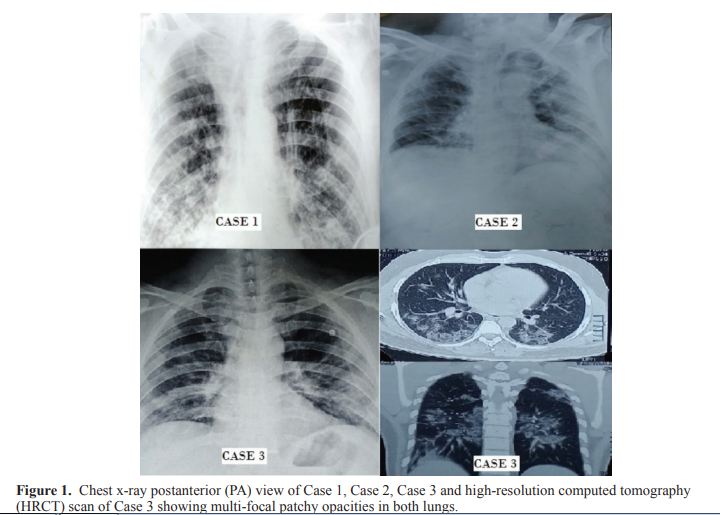

A 67-year-old diabetic male, chronic smoker (40 pack years) was admitted in S.M.S. hospital with the chief complaints of cough and sore throat since 8 days followed by fever and shortness of breath since 3 days. His throat swab tested positive for COVID-19 after 3 days. At presentation his vitals BP was 134/78 mm of Hg, pulse rate was 125/min and respiratory rate was 28/min. Respiratory system examination revealed bilateral crepitations. Other systems were normal on examination. His electrocardiogram (ECG) was suggestive of sinus tachycardia with p-pulmonale, right bundle branch block (RBBB) pattern and T wave inversions. Chest x-ray posteroanterior (PA) view (Figure 1 ) was suggestive of chronic obstructive disease (COPD) with right lower lobe pneumonitis. Haemogram showed leucocytosis with neutrophilia and lymphopenia. Markers of inflammation such as lactate dehydrogenase (LDH), C-reactive protein (CRP), pro-calcitonin (PCT), serum ferritin, fibrin degradation product (FDP) and D-dimer were elevated. Dynamic changes of interleukin-6 (IL-6) levels were observed at admission and during treatment course. Patient’s COVID-19 sample came negative on Day 12 and Day 13 of admission. Unfortunately, secondary bacterial infection in lungs landed him into acute respiratory distress syndrome (ARDS) and he needed invasive ventilator support.

An 85-year-old man who was a known case of diabetes mellitus (10 years), hypertension (10 years), hypothyroidism (8years), chronic kidney disease (4 years) and coronary artery disease (4 years) had history of travel to Dubai. He presented with the chief complaints of mild fever, cough, sore throat and shortness of breath and his vitals were- BP 148/82 mm of Hg, O2 saturation 84% on room air and pulse rate of 120/min. His respiratory rate was 25/min. Respiratory system examination revealed bilateral equal air entry with basal creptitations. All other system examination was normal. ECG was suggestive for RBBB pattern and poor R wave progression. Chest x-ray was suggestive of bilateral pneumonitis (Figure 1). During the period of hospitalization leucocytosis with neutrophilia and lymphopenia were seen. His renal function worsened due to concomitant infection and markers of inflammation were elevated along with IL-6 (Table 2). Throat swabs were sent regularly for COVID-19 testing which came negative on Day 5 and on Day 6 of admission. He was discharged and advised home isolation of 14 days with strict glycaemic control.

A 58-year-old male, health-care professional, resident of Bhilwara (Manchester of India: one of the cluster hotspots in Rajasthan) with comorbidities of hypertension, diabetes mellitus and hypothyroidism for 8 years presented with chief complaints of fever and dry cough in the past 7 days followed by shortness of breath in the past 3 days. His blood pressure(BP) was 150/90 mm of Hg and pulse rate was 97/min, O2 saturation was 90% on room air at the time of presentation. ECG was suggestive of hypertensive changes. Computed tomography (CT) scan (Figure 1 ) showed multifocal patchy peripheral and ground glass opacities in both lung parenchyma, involving both lobes suggestive of viral pneumonitis. Gradually with treatment disease remission started and symptoms ameliorated. On the 6th day of his admission, his oropharyngeal sample came negative for COVID-19 with a repeat negative after 24 hrs. He was discharged and advised home isolation for 14 days.